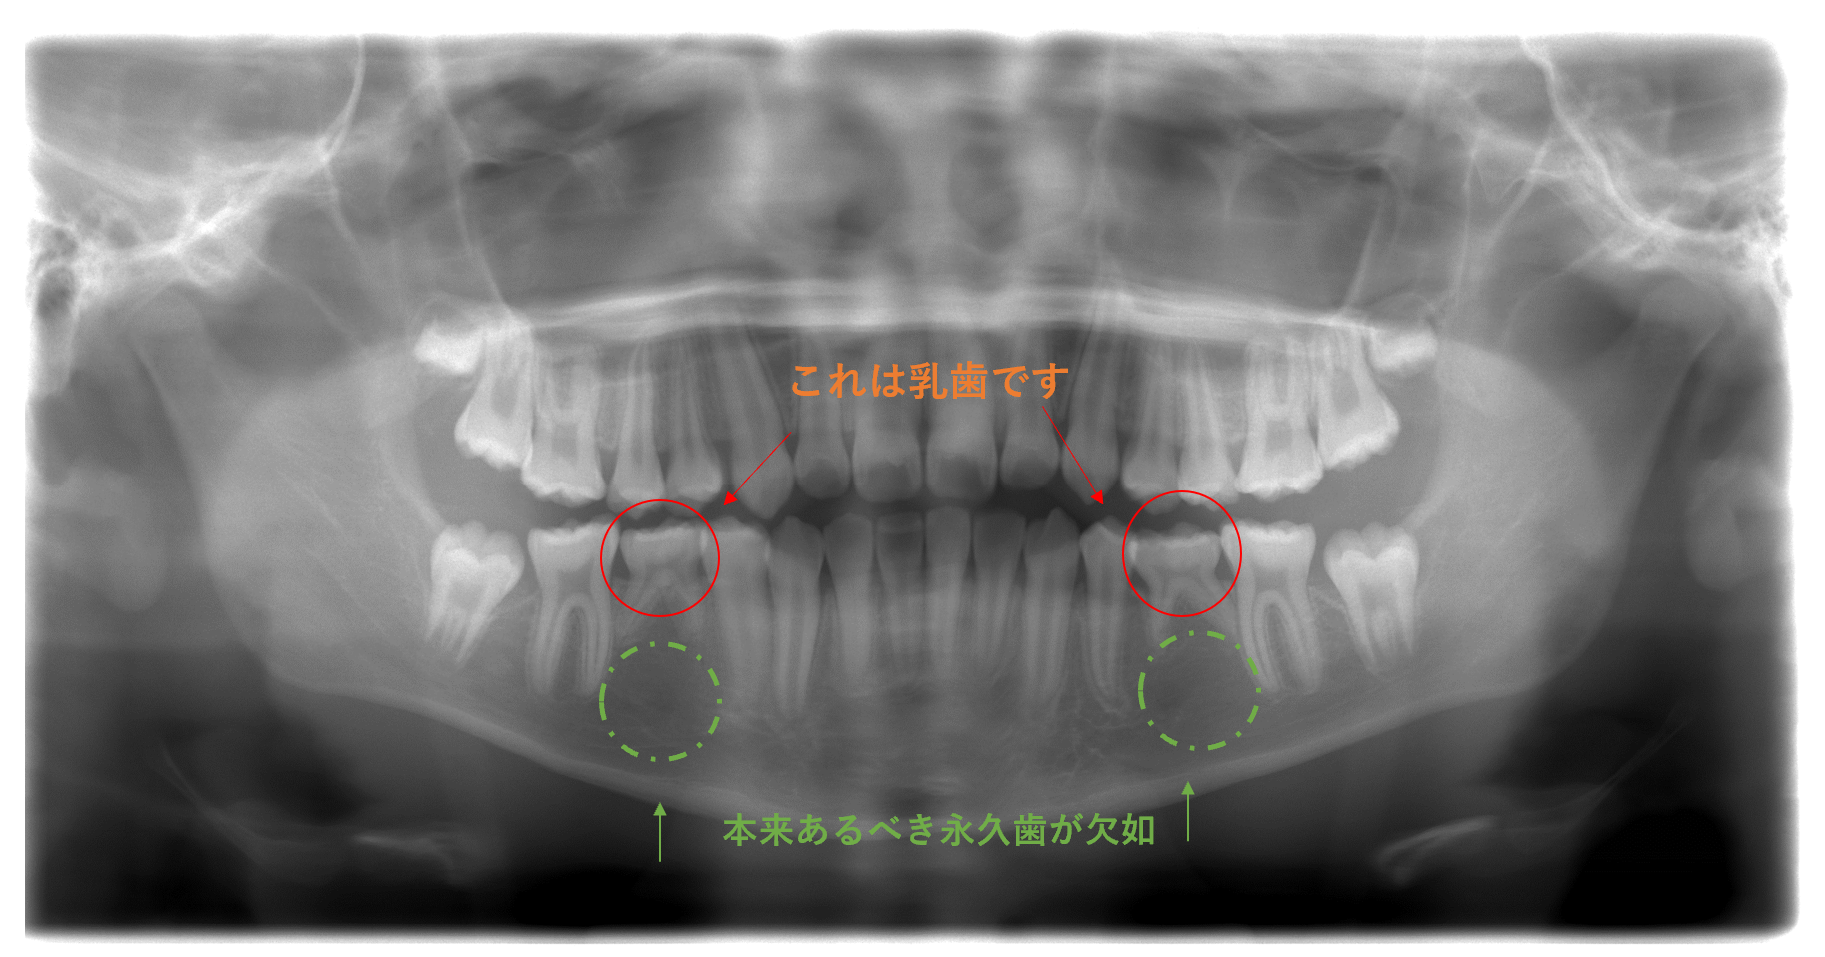

こちらのレントゲンをご覧ください

赤丸は乳歯です。本来その下から永久歯が控えているはずなのに

黄緑の〇の所には、何も映っていません。

日本小児歯科学会学術委員会の「日本人小児の永久歯先天性欠如に関する疫学調査」によると

7歳以上の小児15,544人を対象にした調査で、永久歯の先天性欠如が見られたのは

1,568人、発生頻度が10.09%とのことでした。

10人に1人は先天性欠如とみられるとのことです

意外と発生頻度が高いと思いませんでしたか?

このように先天性欠如があった場合、乳歯を一生使わなくてはなりません!!